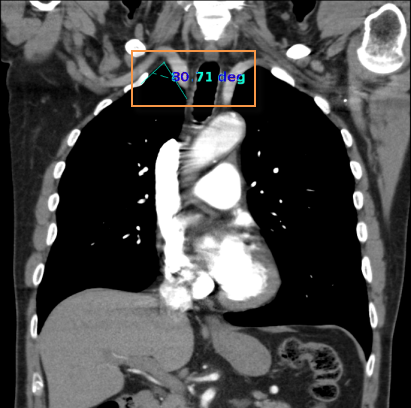

Szög méréséhez: